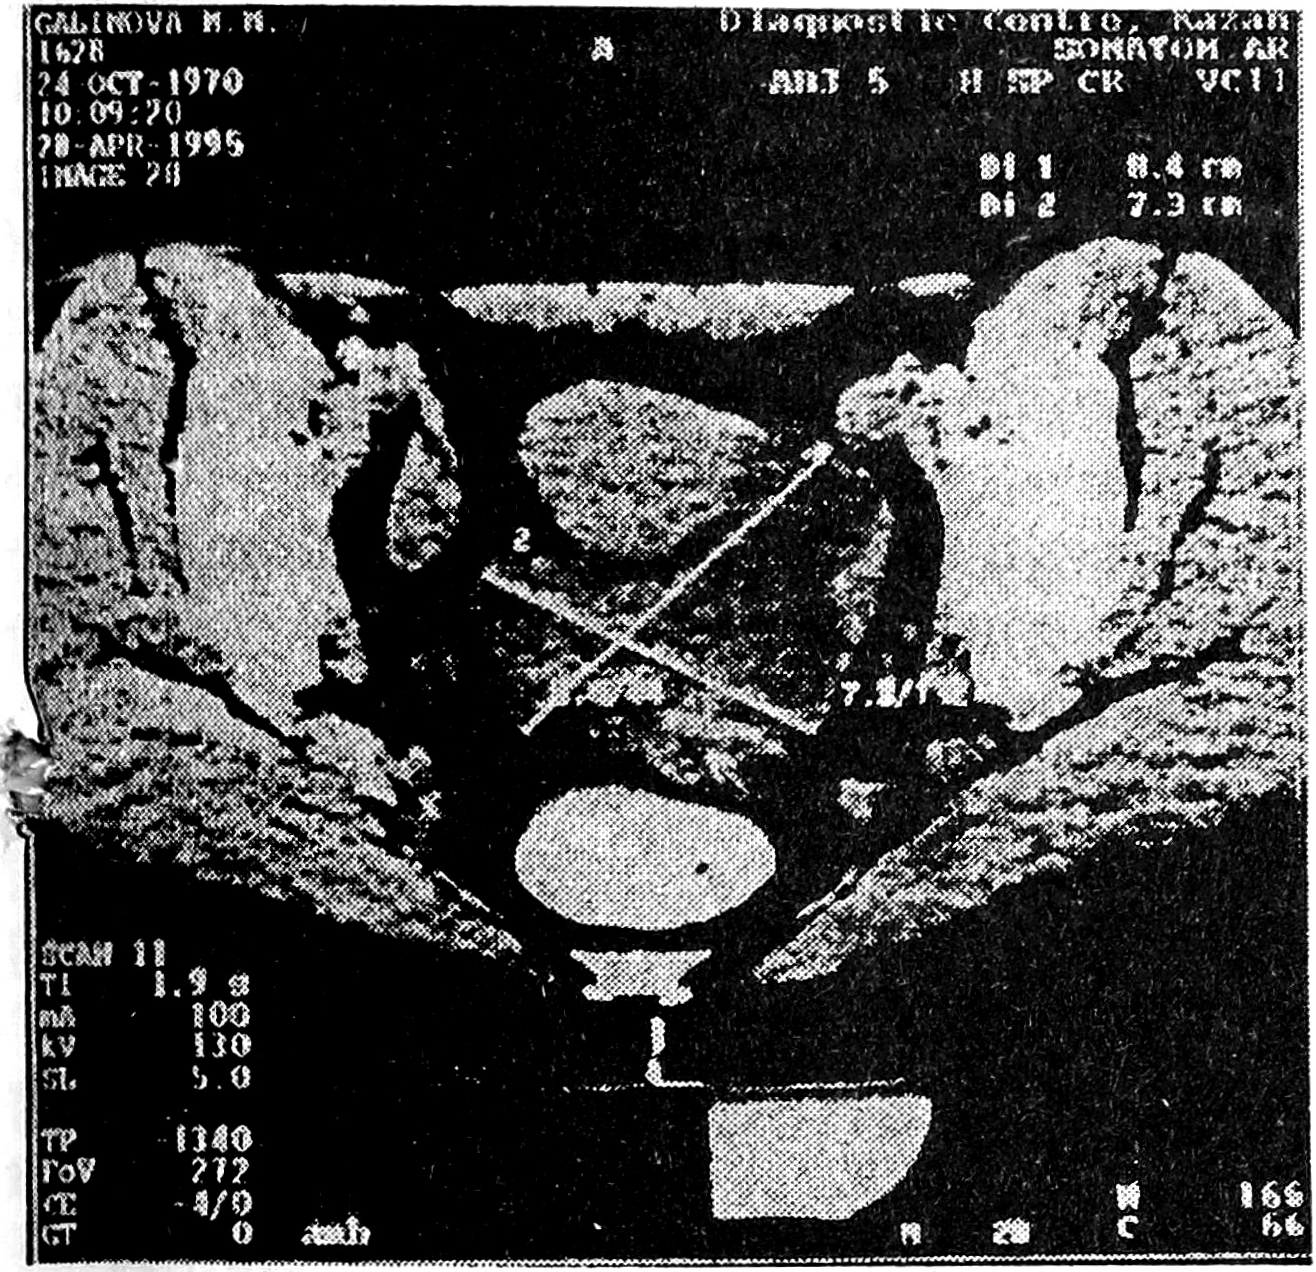

Р., 46 лет, поступила 10.04.1995 г. с жалобами на кровянистые выделения из половых путей с начала марта, которые усилились в течение последней недели, и на боли в нижней части живота и в области поясницы. В анамнезе указаны 2 беременности, одни роды, один аборт, воспаление придатков. Соматический анамнез и статус не отягощены. При осмотре через задний свод определяется малоподвижное образование (6 x 5 см), резко болезненное при пальпации.

Данные УЗИ: слева за маткой имеется образование (85 X 35 мм), размер камер — 45 х 41 мм и 55 X 32 мм, структура образования гипоэхогенная, по внутреннему контуру видны пристеночные включения.

Данные компьютерно-томографического исследования: в полости малого таза в области левых придатков визуализируется опухолевидное образование с неоднородной структурой, отчетливыми контурами, плотностью от 20 до 40 ед.Н.

Предварительное заключение: подозрение на муцинозную цистаденому левого яичника. При лапаротомии — матка слегка увеличена (9 х 5 х 6 см), равномерной плотной консистенции. Правые придатки не увеличены, в спайках. Левые придатки замурованы в спайках. После рассечения спаек извлечена левая труба — раздутая, отечная, расширенная до 6 х 8 см. Левые придатки удалены.

Макропрепарат: на разрезе трубы содержимое геморрагическое; слизистая трубы гладкая, зеленоватого цвета. Яичник не увеличен. На разрезе яичника — умеренное количество фолликулов.

Гистологический анализ: хроническое гнойное воспаление в маточной трубе.

Клинический диагноз: левосторонний гематосальпинкс. Двусторонний перисальпингоофорит. Задний периметрит.

Диагностика в данном случае была достаточно сложна в связи с образованием тубоовариальной опухоли, наличием гематосальпинкса и обширного спаечного процесса (рис. 4).

Рис. 4. Левосторонний гематосальпинкс у больной Р.